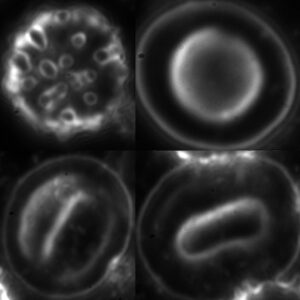

A Lyme borreliosis, azaz a Lyme-kór világszerte a leggyakoribb állatról emberre terjedő fertőzés, és egyben a leggyakoribb kullancs által terjesztett bakteriális megbetegedés. A betegség kórokozója a Borrelia burgdorferi nevű baktérium: egy igen mozgékony, hullámos alakú, Borrelia genusba sorolt baktérium, egy Spirochéta, ami kb. 15 mikrométer hosszú és 0,2 mikrométer széles. Teflon-parazitának is emlegetik, mert felszínét különleges anyag burkolja, kevés rajta a felszíni antigén, ezért ahhoz alig kapcsolódhat a szervezetet védő ellenanyag. Kezelés nélkül évekig évtizedekig megbújhat a szervezetben. Ez rendkívüli alkalmazkodása és kiváló védekezőképessége mellett vegetatív alakjainak, az ún. gemmáknak is köszönhető.